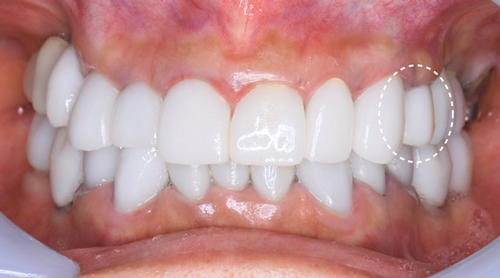

写真は色のチェックです。

手術後から4ヵ月が経ちました。

最初の電話で「インプラントが揺れている!」と聞いて驚きましたが、再度またしっかり噛めるようになって喜ばしい限りです。